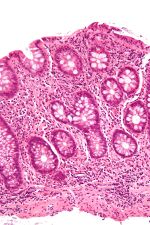

Cryptitis high mag.jpg

A micrograph demonstrating cryptitis, a microscopic correlate of colitis. H&E stain.